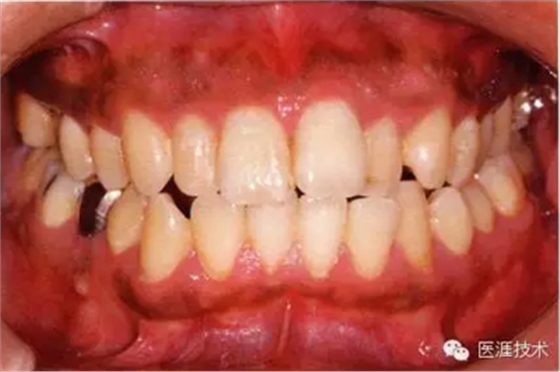

22歲男性牙齦炎的臨床圖像

22歲男性,抽煙(1天約15根,煙齡5年)。刷牙狀態(tài)不佳。抽煙者特有的纖維性牙齦,未見(jiàn)發(fā)紅、腫脹。探針觸診,所有部位均出血。X線牙片未見(jiàn)骨吸收,診斷為牙齦炎。